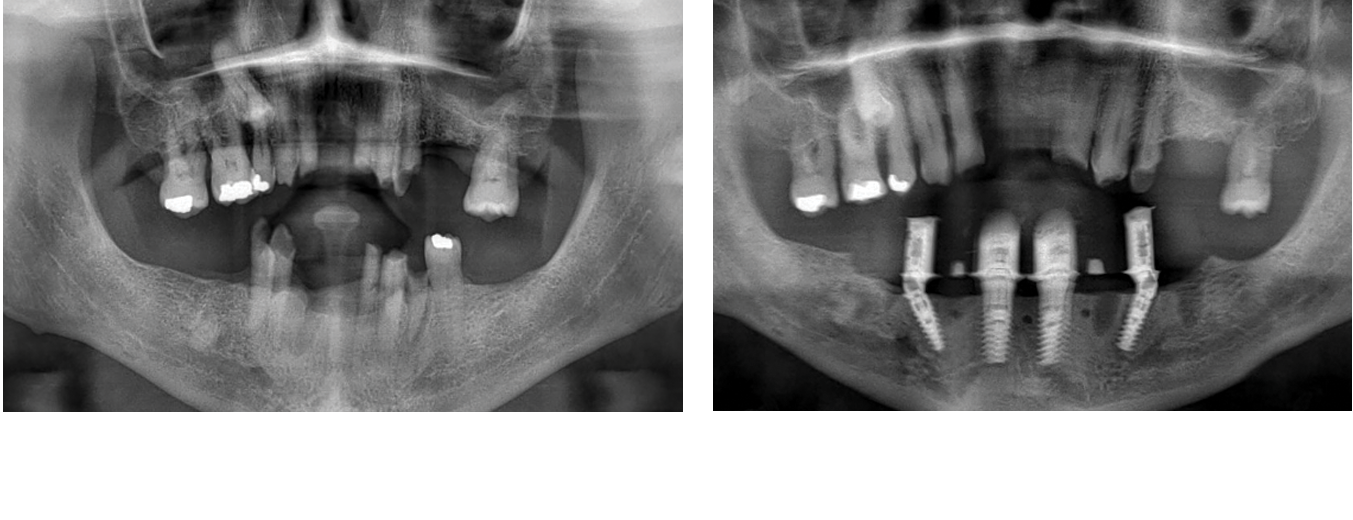

Join an elite group of clinicians for a 3-day immersive program where you’ll treat 3 full arch patients using state-of-the-art techniques: free-hand, guided surgery (flapless), and stackable guides with bone reduction.

Join a small group of experienced clinicians for an intensive hands-on program where you’ll place 15+ implants on real patients under expert supervision.

Sharpen your sinus lift skills with hands-on training, live patient cases, and expert-led sessions.